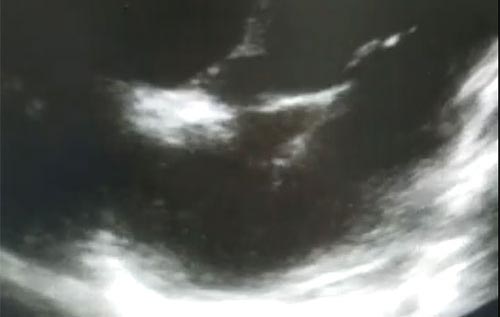

Semana 12

Paciente 30 anos IC prévia, hepatopata, com COVID confirmado. O que podemos ver na imagem?